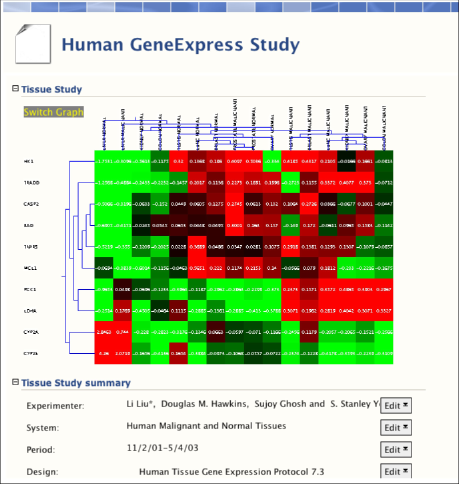

BioDASH is currently being expanded to handle gene expression data, merged with clinical, histological, and toxicity findings, all linked through RDF-OWL:

Gene expression data from malignant and normal tissues based on GeneLogic's GeneExpress database were obtained from the work of Liu et al., 2003. The expression table files were converted into RDF using an Excel script.

Aggregates of biological and molecular data will be used to create new knowledge repositories for use in medical research and drug discovery.